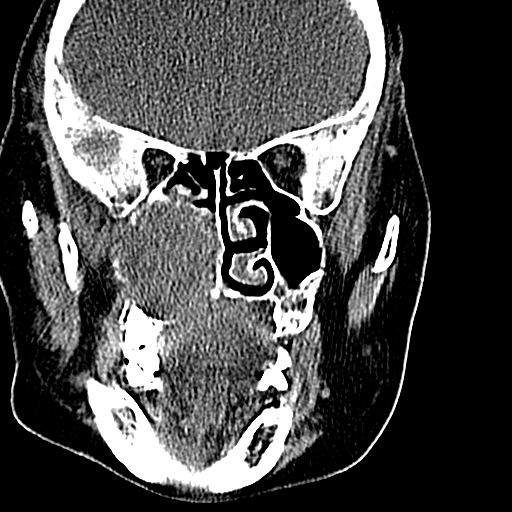

标题: CT19708:单侧上颌窦病变 [打印本页]

标题: CT19708:单侧上颌窦病变

老年患者,女。鼻塞多年。

考虑右侧上颌窦良性占位性病变,粘液囊肿可能性大;建议活检。

膨胀性生长,且骨质无破坏,说明时间久,良性;从密度,边缘看,内部还见坏死区,应该是实性肿瘤,定性,影像学无绝对的特异性

病灶密度很不均匀,骨壁膨胀中有断裂,考虑内翻乳头状瘤可能性大,粘液囊肿不排除

膨胀性生长,且骨质无破坏,说明时间久,良性;从密度,边缘看,内部还见坏死区,应该是实性肿瘤,定性,影像学无绝对的特异性,考虑内翻性乳头状瘤可能